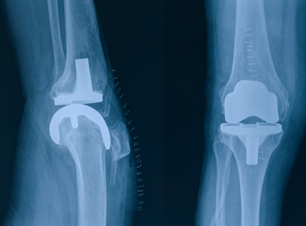

Artritis, problemas de caídas, traumas, bursitis, artroscopía, resbalones, accidentes, tratamientos para problemas, enfermedades.